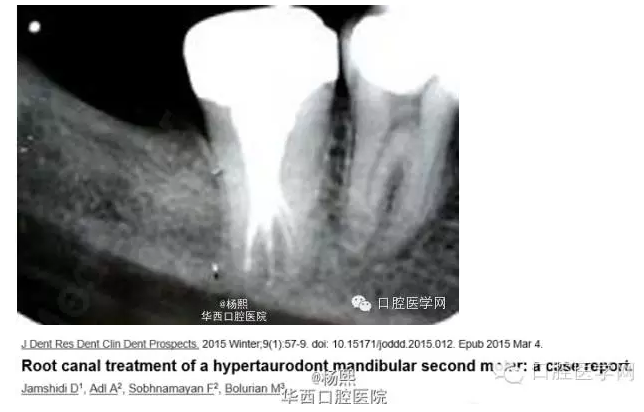

這個病例挺有意思的,分享給大家。病例為JamshidiD,Adl,Sobhnamayan,F(xiàn),Bolurian M.J Dent ResDent Clin Dent Prospects.2015 Winter;9(1):57-9.doi:10.15171/joddd.2015.012.Epub 2015Mar4.